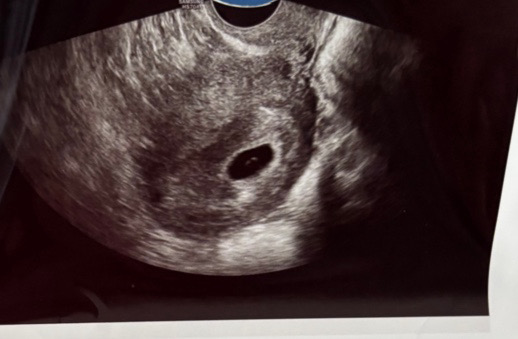

난황크기좀봐주세요

막생6월4일이구 아기집 6월12일에 난황 조금하게보고 오늘병원다녀왔는데 아기집이좀작고난황크기가좀큰편이라구 심장소리도못듣고왔어요ㅜㅜ 네이버주수로 7주입니당